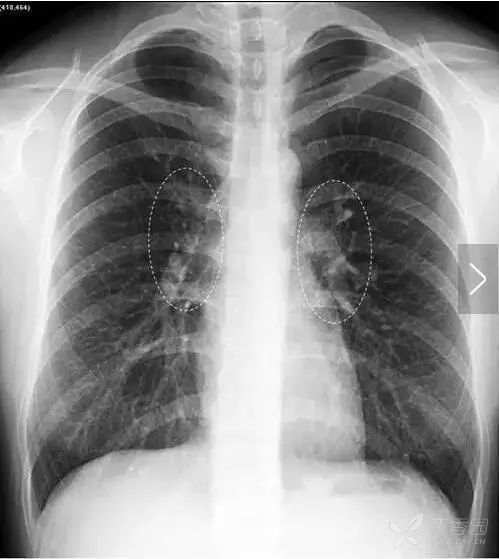

乳 头 乳头有可能会在正位胸片的两肺下野形成直径约1cm的小圆形投影,年龄偏大的妇女更容易出现这种情况。

上图双侧乳头投影(白色箭头)。位于第六前肋水平,两侧比较对称的小圆形阴影。

乳头影须和肺内小结节病灶鉴别,方法是:①双侧乳头的投影的位置通常相对比较固定,多位于两肺下野第5、6前肋处附近。②其位置和大小往往两侧比较对称。如果不易和肺内病灶区别,透视下转动患者体位即可与肺野分开,或采取进一步检查的措施。